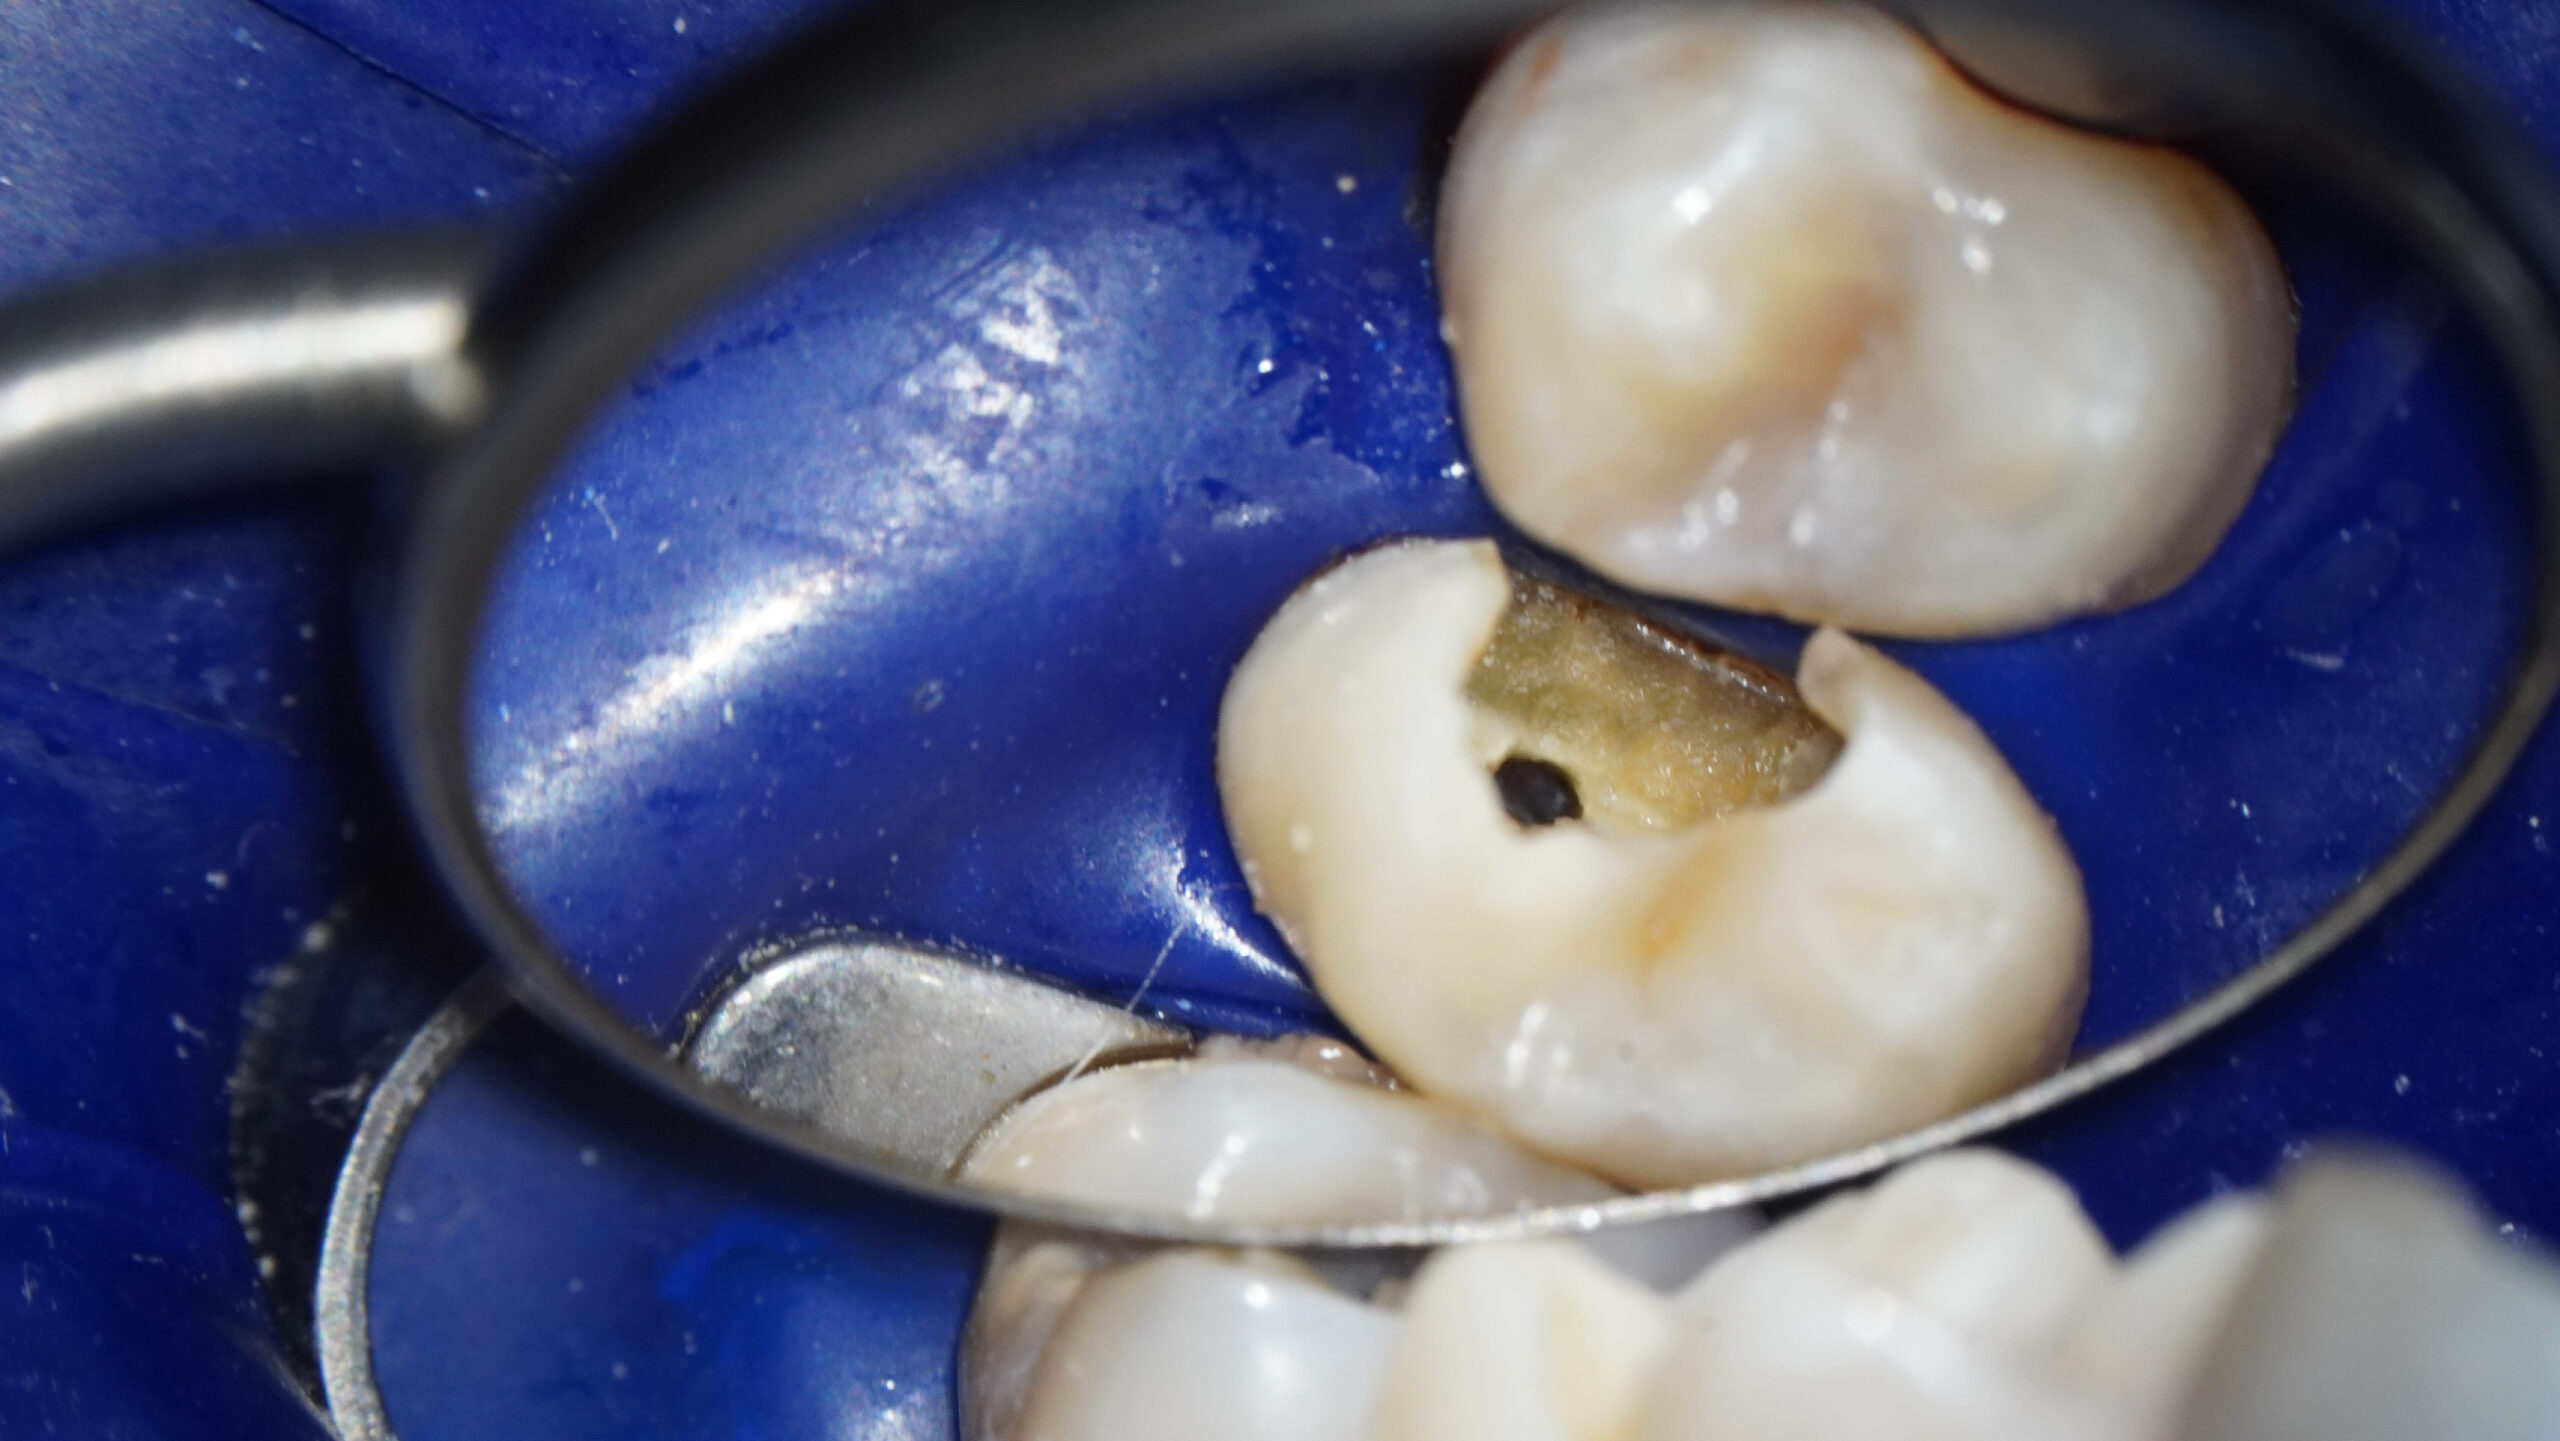

* Haz click sobre las imágenes para verlas a mayor tamaño

Haz click sobre las imágenes para verlas a mayor tamaño y a color